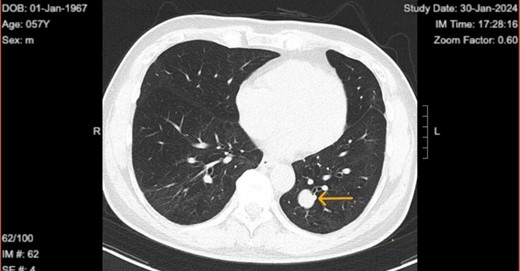

The patient is a 57-year-old male in the United States, who is a non-smoker with good past health. He had no history of occupational exposure to silica, beryllium, or asbestos. He presented with fever and dyspnea and attended the ER, where he was diagnosed with COVID-19 infection and a lung nodule. He underwent a computed tomography (CT) scan of the chest as a part of their diagnostic workup for suspected COVID-19 infection. Chest CT on 21 May 2021 revealed the presence of a well-demarcated non-calcified solid nodule of 1.5 × 1.3 cm in the left lower lobe of the lung (Fig. 1). It was suspected to be a lung carcinoma at first. CT-guided lung biopsy was recommended for further diagnosis.

Chest computed tomography in 2022 revealed well circumscribed solitary lung tumor of 1.5 × 1.3 cm in size.